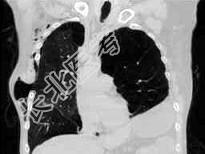

- 单项选择题男,68岁, 胸闷、气短1年余,加重1周, 右胸有手术史,结合CT图像, 最可能的诊断是 ( )

A、右侧气胸并皮下气肿、左侧肺气肿

B、右侧气胸并皮下气肿、左侧肺不张

C、双侧肺气肿

D、右侧气胸并皮下气肿

E、右侧肺间质病变、左侧肺气肿